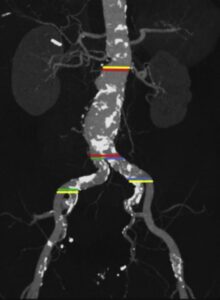

🔹 کشف نکته کلیدی: نقش آرتفکت Blooming

دکتر نیکنهاد در یک مطالعه تحلیلی، به نکتهای ظریف اما بسیار مهم اشاره کرده است:

کلید این معما، آرتفکت تصویری موسوم به Blooming Artefact است.

این پدیده در تصویربرداریهای اولتراسوند و سیتی رخ میدهد؛ به این صورت که دانسیتههای کوچک و اکوژن در مواجهه با امواج صوتی یا اشعه ایکس، بزرگتر از اندازه واقعی خود نمایش داده میشوند.

در نتیجه، پلاکهای کوچک کلسیفیه ممکن است بهصورت رسوبات وسیع و انسدادی گزارش شوند، در حالی که لومن واقعی رگ باز و جریان خون کافی است.

🔹 شواهد تصویری

در نمونههای ارائهشده، دو مورد از بیماران با پلاکهای ظاهراً گسترده در سیتیاسکن بررسی شدند.

اما پس از انجام آنژیوگرافی عروقی، مشخص گردید که:

-

لومن واقعی عروق بهطور قابل ملاحظهای باز است،

-

میزان انسداد کمتر از آن چیزی است که در سیتی دیده میشود،

-

و تصمیمگیری جراحی بر اساس یافتههای واقعی میتواند با اطمینان بیشتری انجام گیرد.

این موارد نمونهای از تفاوت بین برداشت تصویری ناشی از Blooming Artefact و واقعیت آناتومیک هستند.